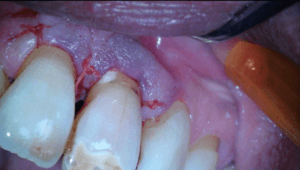

Na polijsten hechtten we de flap en maakten we een afspraak voor een week later.

Toen we de patiënt terug zagen na drie maanden was het aspect van de 11 weer gezond. De pocket was gereduceerd, er was geen pusafvloed meer en het tandvlees zag er gezond uit.

Achteraf analyserend kunnen we stellen dat de situatie niet ideaal is. Er is een composietrestauratie gemaakt in het meest kwetsbare deel van het element en de restauratie ligt gedeeltelijk nog onder de gingiva. We hopen dat het lang goed gaat maar lekkage ligt op de loer natuurlijk en wellicht is het nodig om na een aantal jaren opnieuw een flapje te doen en de restauratie te vernieuwen.